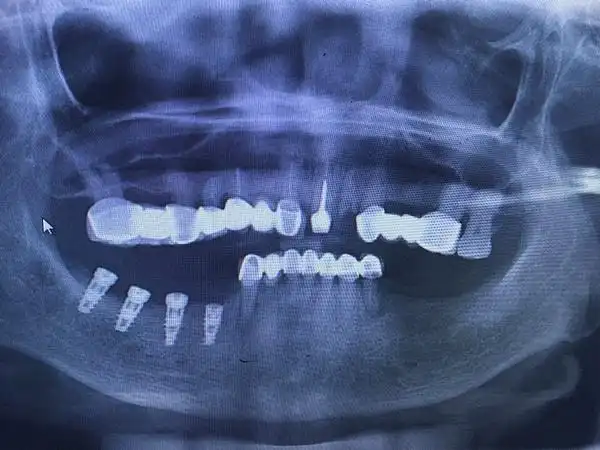

我们也完全相信,妈妈很快就会体会到现在植入的这4颗种植体